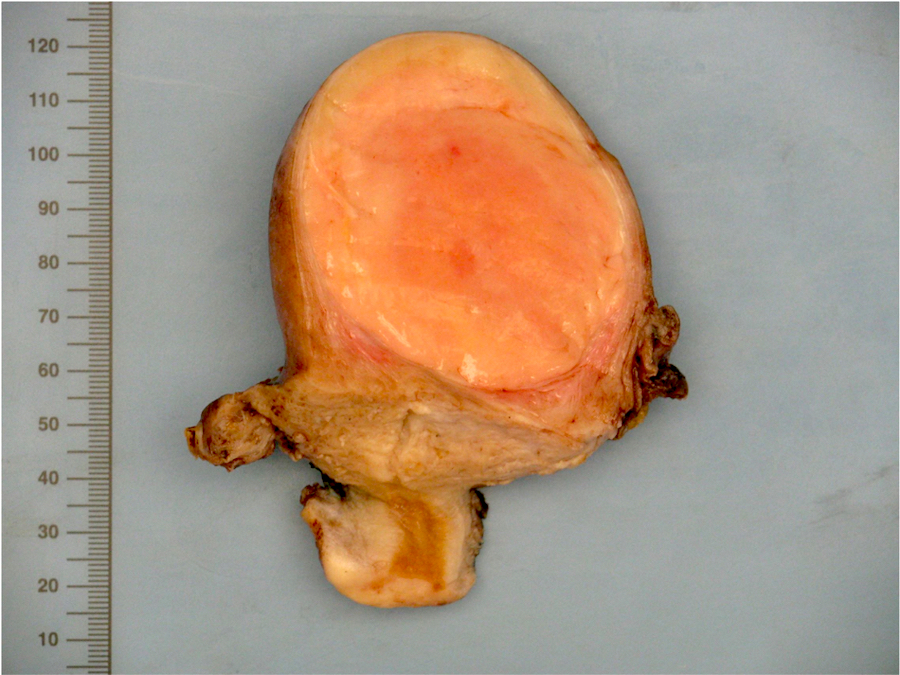

Gross description

- Poorly circumscribed soft yellow-tan to white nodules extending from the endometrium and invading into the myometrium

- Worm-like plugs of tumor may be seen in the myometrium or lymphovascular channels (Am J Surg Pathol 1990;14:415)

- Often with a polypoid endometrial component

- May appear deceptively well circumscribed: extensive sampling of the tumor myometrial interface is necessary to rule out endometrial stromal nodule (Int J Gynecol Pathol 2014;33:374)

- Hemorrhage and necrosis may be seen

Gross images

Contributed by Elizabeth Kertowidjojo, M.D., Ph.D., M.P.H. and Ayse Ayhan, M.D., Ph.D.